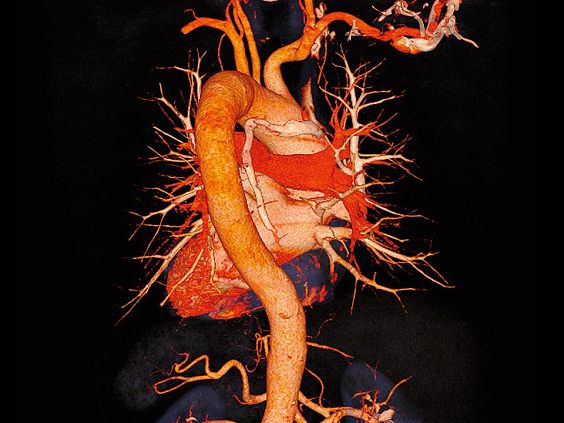

SOMATOM go.Up позволяет проводить высококачественные ангиографические исследования сосудов с хорошим контрастным усилением, субмиллиметровыми срезами и точной синхронизацией по времени.